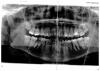

Nightflight Опубликовано 12 февраля, 2011 Поделиться Опубликовано 12 февраля, 2011 Здравствуйте! Первый раз в жизни сознательно занимаюсь своими зубами и, конечно, возникает много вопросов. Очень здорово, что есть этот форум, где можно проконсультироваться по всяким спорным ситуациям! В этот раз хотелось бы получить еще одно мнение вот по такому вопросу. Летом 2007 г. мне поставили пломбу на нижнюю левую шестерку (зуб болел при надкусывании, реагировал на сладкое). Несмотря на лечение, неприятные ощущения остались. Когда через пару недель я пришла к тому же стоматологу с повторной жалобой на этот же зуб, врач сказала, что болей быть не должно, т.к. она все вычистила. Со временем пройдет. Прошло 4 года. Боль при надкусывании (и при надавливании - причем только со стороны контакта с пятеркой, т.е. не по всей поверхности зуба. Достаточно было пальцем нажать на эту сторону зуба, чтобы стало больно) не прошла. Две недели назад по моей просьбе зуб расковыряли и определили под вкладку (зуб живой). По словам врача, ничего страшного она в нем не нашла, была только подозрительная полость. На время изготовления вкладки поставили временную пломбу. По времени это совпало с пломбировкой каналов в шестерке над этим зубом (резорцированный зуб, пойдет под коронку), который тоже пока закрыли временной пломбой. Сразу же после этого нижняя шестерка начала болеть. Ну то, что жевать на левой стороне было больно, мне объяснили тем, что пломбы временные. Но помимо этого, все две недели по вечерам шестерка начинала ныть, после чего боль передавалась на верхнюю шестерку (ту, которая с каналами), охватывала обе челюсти с левой стороны и начинала отдавать в ухо. После этого у меня оставалось два варианта действий: кетанов или цианистый калий. Кетанов помогал. По утрам боли не было совсем, все представление начиналось около 8-9 вечера. Сегодня я наконец-то попала к врачу. Нижнюю шестерку опять расковыряли, еще раз убедились, что она чистая (мне даже на экране показали - абсолютно белый зуб, стенки высокие, никакого намека на кариес, десны в порядке - при прикосновении ничего не болит). Простучали рядом стоящие зубы - ничего. Решили все-таки ставить вкладку. Было очень больно, анестезия переставала действовать через полчаса, зуб очень сильно реагировал даже на воду и воздух. Под вкладкой при нажатии зуб по-прежнему немного реагирует, но не так сильно, как под пломбой. Мой врач полагает, что проблема не в шестерке, а в левой восьмерке, которая из-за стресса и переутомления (кошмарные были две недели на работе) активизировалась и начала толкать все остальные зубы (плюс на том кусочке, который уже вылез, кариес). Мне назначили сумамед и сказали удалять восьмерку как можно скорее. Если после этого боль останется - придется расковыривать и убивать шестерку. Как вы оцениваете такой план? Действительно ли шестерка может болеть из-за того, что режется восьмерка? Снимок есть только до начала лечения. Ссылка на комментарий